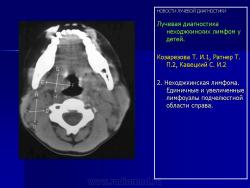

Лучевая диагностика неходжкинских лимфом у детей.

Козарезова Т. И.1, Ратнер Т. П.2, Кавецкий С. И.2

Первая — область верхнего средостения (от грудино-ключичного соединения до бифуркации трахеи). Вторая — нижний отдел грудной клетки на уровне кардиодиафрагмального угла). Третья — верхний отдел живота (от ножек диафрагмы до ворот почек). Четвертая — нижний отдел живота (на уровне бифуркации аорты). Пятая — малый таз (наружные и внутренние подвздошные ЛУ). В связи с этим по данным КТ выделяют 4 вида поражения лимфатических узлов: 1) изолированную форму — поражение ЛУ в виде одиночных увеличенных более 5-8 мм (Рис. 2) и не связанных между собой структурно; 2) пакет ЛУ — группа изолированных узлов, тесно соединенных между собой; 3) конгломерат ЛУ — образование, представляющее собой одну или несколько групп узлов, как единое целое; 4) лимфоидный инфильтрат — патологическая лимфоидная ткань, имеющая нечеткие края, и, как правило, располагающаяся по ходу поясничных и грудного лимфатических стволов. При КТ исследовании основным критерием поражения лимфоузла являются его размеры. По данным литературы критерием поражения одного лимфоузла считается увеличение его до 15 мм и более. Для нескольких лимфоузлов одной группы — 10-12 мм, в различных группах — 8-10 мм (ретрокруральные — 6 мм).